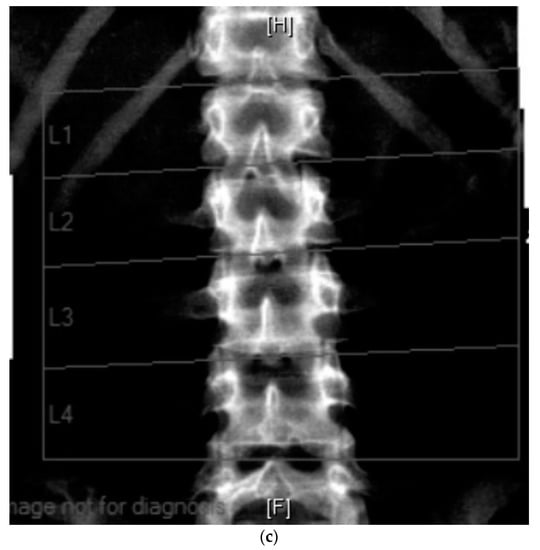

The effectiveness of supportive management can be evaluated by DEXA scan (Figure 3), a gold standard method for monitoring the progression of bone mineral density decline. The whole spine x-ray (Figure 2) can be used for identification of bone deformities and fractures. QCT however is the sensitive quantitative method used to assess the bone mineral density. Body composition has become increasingly utilized in Inherited Metabolic Disorders field and provides additional information about the bone and muscle involvement.

Figure 3.

(a) 23-year-old male with PMM2-CDG (BMI 17 kg/m2). DEXA scan: Results: bone mineral density below expected range for age. Evidence of moderate compression at T8 and T9 vertebrae. (b) DEXA scan: Lumbar spine (L1–L4): T-score −3.5, Z-score −3.5, bone mineral density 0.8 g/cm3.